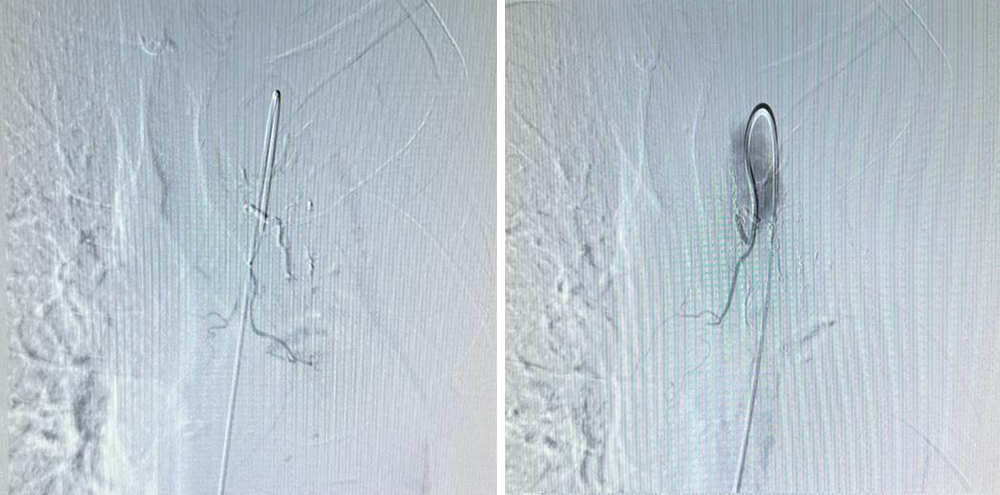

在气管分叉处主动脉偏左前壁找到左侧支气管动脉

经造影后可见造影剂异常外渗,明确出血靶血管

应用医用胶+明胶海绵颗粒行充分栓塞,栓塞后反复造影可见出血血管闭塞,异常染色消失,达到栓塞充分效果,患者无不良事件发生。